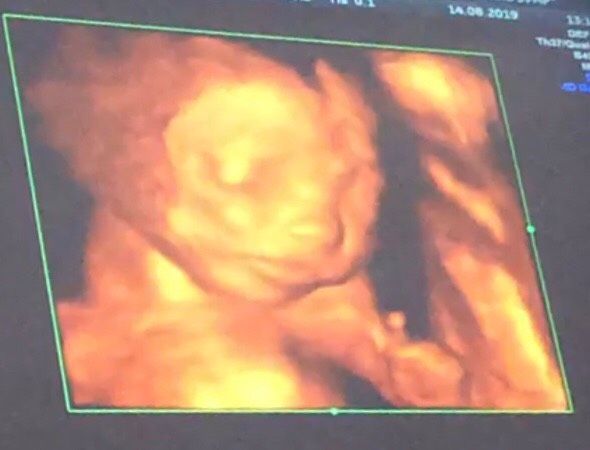

Прошли второй скрининг!??

Дочку подтвердили уже 100%??

Сказали всё прекрасно, ребёнок абсолютно здоров (Узист моя — заведующая отделения по паталогиям).

Для моего спокойствия пригласила ещё главного генетика и они в два голоса сказали мне слать врачей ЖК на все 4 стороны, так как дочка здоровенькая и… красотка ??♀️

Всё тщательно посмотрела в этот раз, рассказывала подробно и даже бонусом сделали фотокарточку 3D (губку за одно проверили — целенькая ??).

Личико у неё такое трооооогательное, как будто сейчас заплачет (но это может быть не объективно ? ибо раньше мне казались все 3D снимки с Узи какими-то ужасными ??)